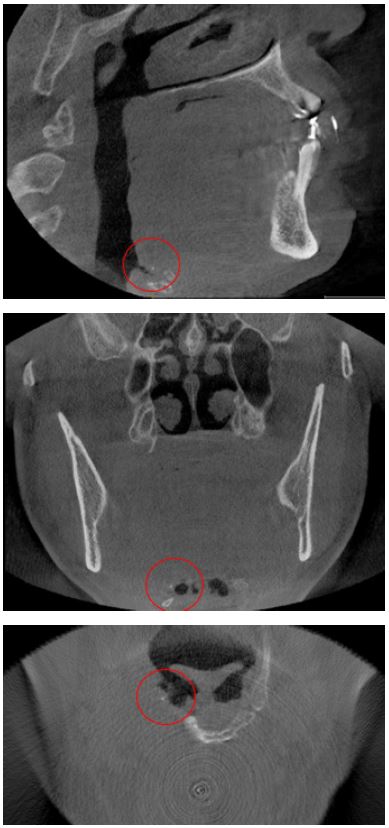

Los tonsilolitos encontrados afectaron, principalmente, a las amígdalas palatinas (figura 1), con un 96,8 % (n = 120); a las amígdalas linguales (figura 2), con un 2,4 % (n = 3); y, finalmente, a las amígdalas nasofaríngeas (figura 3), con un 0,8 % (n = 1) (tabla 10).

Imágenes tomadas del archivo del Servicio de Radiología Bucal y Maxilofacial del CDD-UPCH (sede San Isidro).

Los tonsilolitos fueron encontrados principalmente en la amígdala palatina, en un 96,77 % (n = 120); seguido de la amígdala lingual, en un 2,42 % (n = 3); de las amígdalas nasofaríngeas, 0,81% (n = 1); y finalmente no se encontraron tonsilolitos en las amígdalas tubáricas. Ello coincide con distintos informes (8,10,11), que muestran que los tonsilolitos palatinos son uno de los hallazgos más comunes entre las calcificaciones patológicas en la región de la cabeza y el cuello, oscilando entre el 16 % y el 46,1 %. La alta prevalencia de tonsilolitos en las amígdalas palatinas podría deberse a que estas presentan criptas más profundas, ramificadas y relativamente apretadas. Las amígdalas linguales presentan criptas poco aplanadas, poco ramificadas, bastante separadas unas de otras. Las amígdalas faríngeas y tubáricas no presentan criptas típicas sino pliegues con recesos irregulares. Además, las amígdalas palatinas suelen estar más expuestas a las infecciones crónicas recurrentes, al tabaquismo, a las bebidas alcohólicas y a la mala higiene en comparación con las amígdalas linguales nasofaríngeas (12,15).